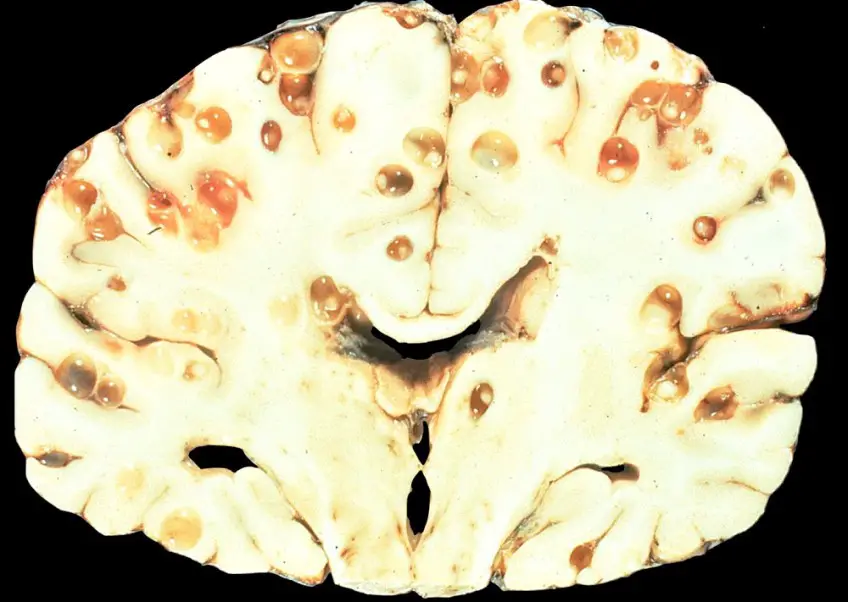

Published 12/02/2018 at 1000 × 711 in Verme solitario: lunghezza, come eliminarlo, trovarlo nelle feci, immagini

MEDICINA ONLINE TAENIA SOLIUM TENIA VERME SOLITARIO INTESTINO pork tapeworm infection